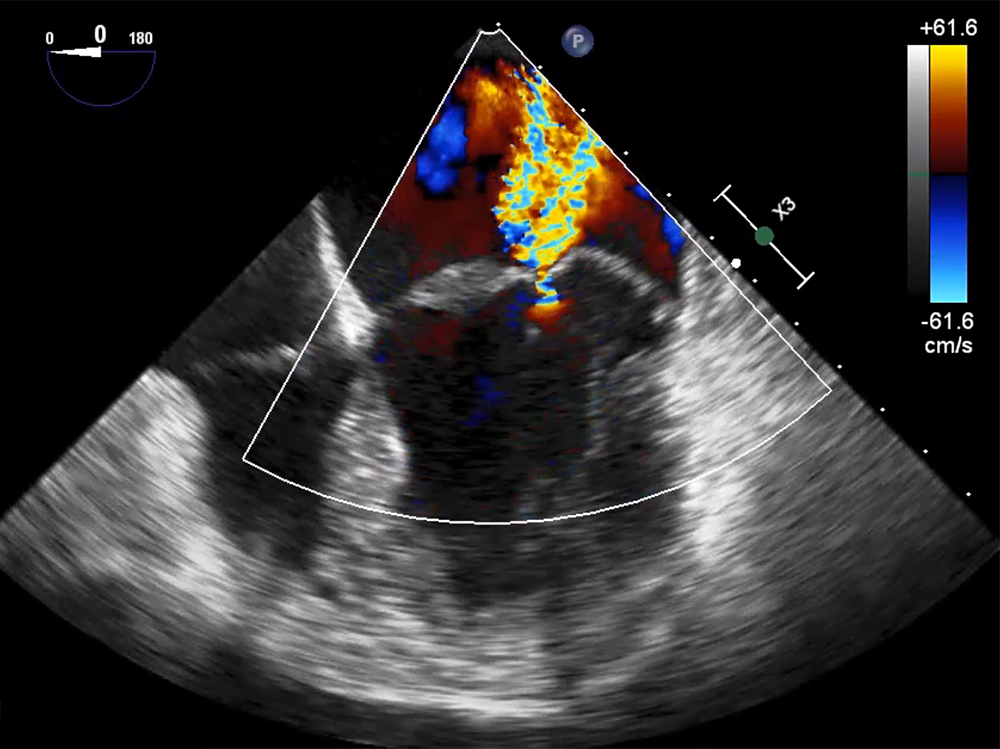

El Ecocardiograma Transesofágico (ETE) es una de las técnicas básicas de la imagen cardíaca. Su uso está sólidamente implementado en la práctica clínica y en las Guías de Práctica Clínica por su capacidad para valorar de forma muy precisa la anatomía y función cardíaca en una gama interminable de patologías cardíacas complejas.El Máster en Ecocardiografía Transesofágica Clínica es una propuesta de la Sociedad Española de Imagen Cardíaca en colaboración con Grupo CTO que busca dar solución a las necesidades crecientes de Formación y Formación Continuada de todo tipo de especialistas interesados utilizar la técnica.